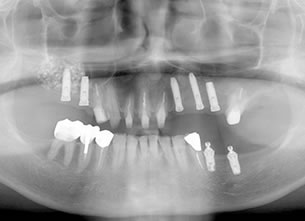

症例1 : 上下顎無菌顎症例

69歳、男性。

• 上顎は両側サイナスリフトと同時に即時荷重を行った。

• 下顎は抜歯即時埋入即時荷重を行った。

• 最終補綴物は、チタンのP.I.B.とM.B.のコンビネーションで修復した。

• 本症例の要旨は第39回日本口腔インプラント学会(大阪)にて症例報告した。